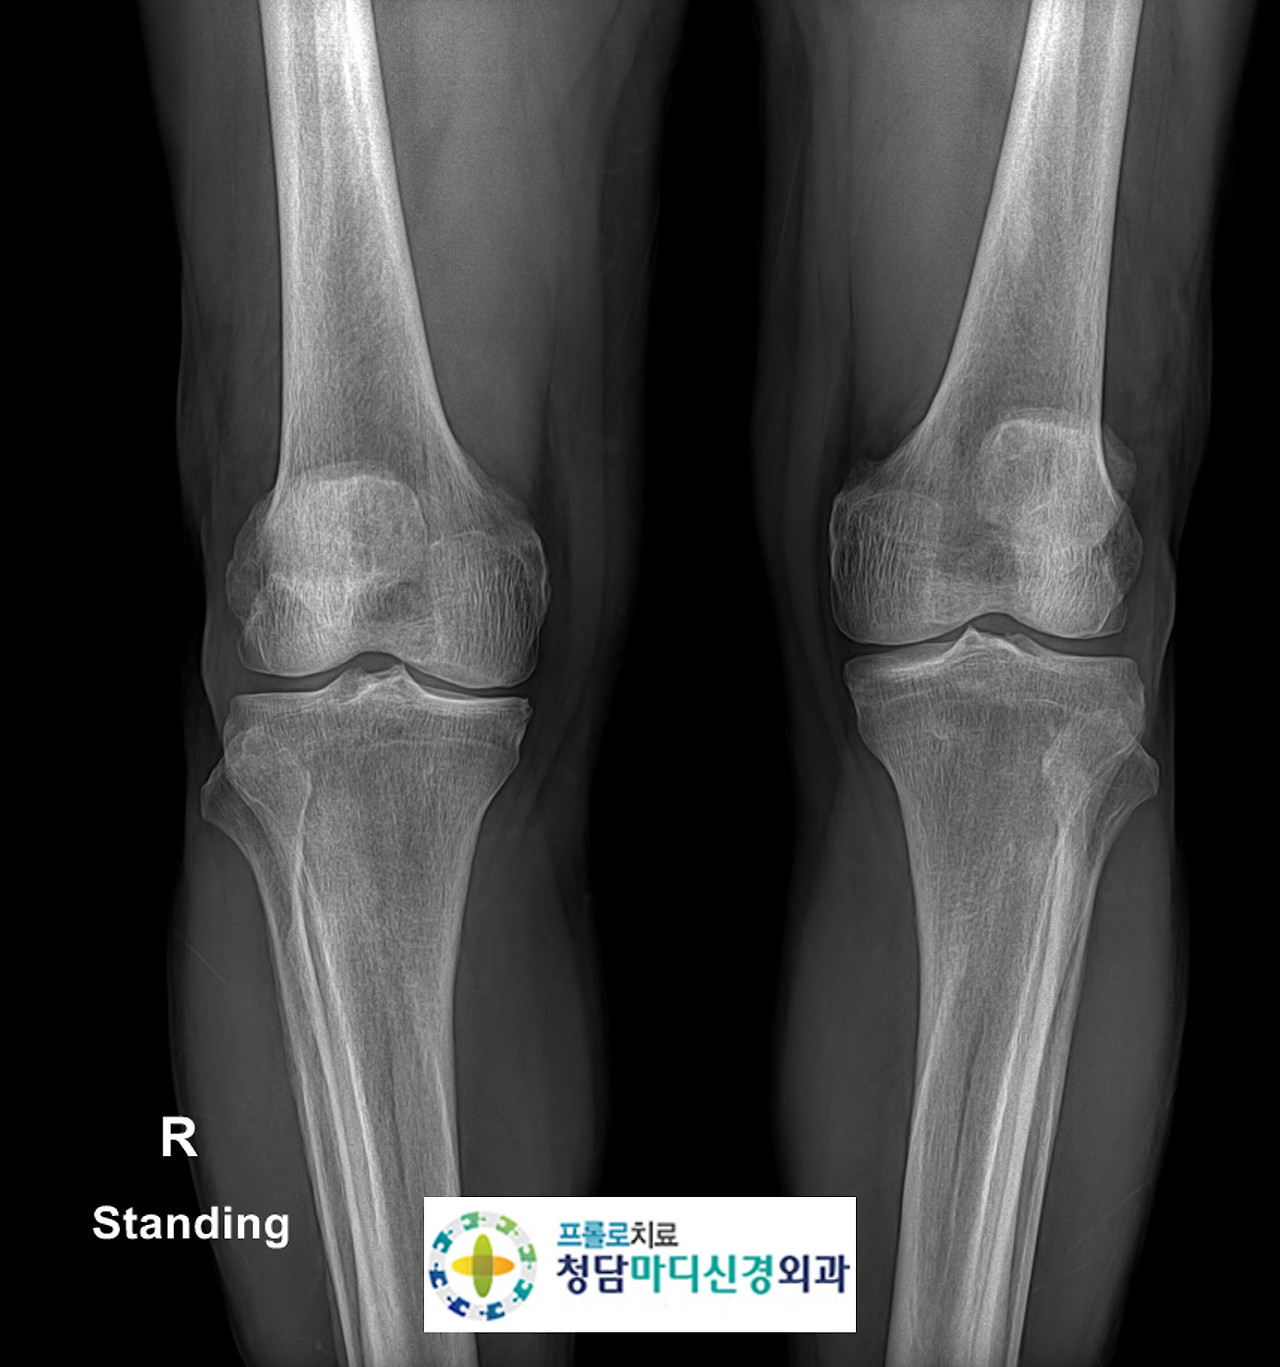

0516(2).jpg 무릎 엑스레이 사진

무릎의 방사선 검사상 켈그렌-로렌스 Gr2 정도의 퇴행성변화를 보이고 있었습니다.